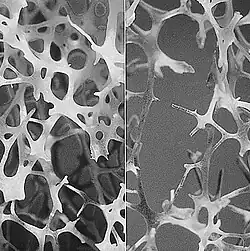

в костной ткани (остеопороз)

Процесс перестройки (ремоделирования) костной ткани происходит в отдельных участках кости, которые носят название «единицы ремоделирования» или базисной многоклеточной единицы (БМЕ). В этих участках локально протекают сопряжённые процессы резорбции и образования кости. Активизация процесса начинается с запуска неких сигналов-стимулов, по которым остеокласты и другие мононуклеарные клетки мигрируют к определённому участку костной ткани и прикрепляются к костной пластине. Остеокласты продуцируют протеолитические ферменты, лактат, ионы водорода, которые разрушают (гидролизуют) белковый матрикс и растворяют минеральную часть кости, при этом выделяется свободный кальций и другие компоненты.[1]:85—87 В результате такой активности в губчатой кости образуются углубления до 40 мкм, имеющие форму блюдца, а в кортикальной кости — конусовидные пустоты диаметром около 150 мкм и длиной до 2,5 мм. Продолжительность фазы резорбции длится от 27 дней в кортикальном слое кости и до 42 дней в губчатой ткани. Этот период резорбции включает в себя и фазу реверсии длительностью 4 дня в кортикальной и 9 дней в губчатой тканях кости. Фаза реверсии является переходным периодом, в который процесс резорбции сопряжён с процессом формирования кости. В период реверсии образуется цементирующая линия (или клей), которая соединяет новую и старую кость. Цикл ремоделирования завершается фазой формирования кости, которая длится от 95 до 130 дней. Вновь образующийся участок костной ткани носит название базисной структурной единицы (БСЕ) или остеона. Остеобласты образуют неминерализованный органический матрикс (остеоид), который через 25—35 дней начинает минерализоваться.[1]:87 Ремоделирование кости начинается ещё в пренатальном периоде и продолжается на протяжении всей жизни. Активность ремоделирования костной ткани и скорость костеобразования находятся на высоком уровне вплоть до достижения индивидом половой зрелости, затем этот уровень снижается. В среднем к 20—23 годам жизни достигается пик костной массы, который поддерживается на заданном уровне до 30—35 лет у женщин, а у мужчин — несколько дольше. В этот возрастной период ремоделирование кости имеет циклический равномерный характер, в котором процессы разрушения и образования кости уравновешены, что обеспечивает обновление кости и сохранение костной массы, а также поддерживает минеральный обмен. С возрастом интенсивность ремоделирования костной ткани резко снижается, это происходит после 35 лет у женщин и 50 лет у мужчин. Резорбция костной ткани идёт с бо́льшей скоростью, чем костеобразование, начинается постепенная потеря массы кости, что становится причиной возрастного уменьшения костного объёма и снижения минеральной плотности костной ткани (МПКТ).[2]:12